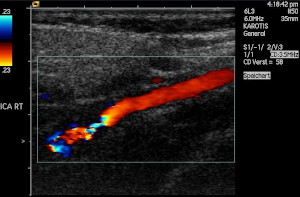

Ultrasound and the Doppler effect (ESCMR)

Ultrasonic waves (ultrasound) are sound waves with a frequency greater than \(\text{20 000}\) \(\text{Hz}\) (the upper limit of human hearing). These waves can be used in medicine to determine the direction of blood flow. The device, called a Doppler flow meter, sends out sound waves. The sound waves can travel through skin and tissue and will be reflected by moving objects in the body (like blood). The reflected waves return to the flow meter where its frequency (received frequency) is compared to the transmitted frequency. Because of the Doppler effect, blood that is moving towards the flow meter will change the sound to a higher frequency and blood that is moving away from the flow meter will cause a lower frequency.

Ultrasound can be used to determine whether blood is flowing in the right direction in the circulation system of unborn babies, or identify areas in the body where blood flow is restricted due to narrow veins. The use of ultrasound equipment in medicine is called sonography or ultrasonography.

Colour Doppler imaging of cervicocephalic fibromuscular dysplasia